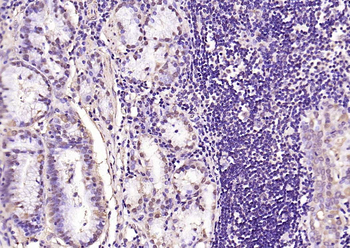

Phospho-Smad3 (Ser423 + Ser425) Rabbit Polyclonal Antibody [orb6983]

FC, IF, IHC-Fr, IHC-P, WB

Bovine, Canine, Equine, Gallus

Human, Mouse, Porcine, Rat

Rabbit

Polyclonal

Unconjugated

100 μl, 200 μl, 50 μlPhospho-SMAD5 (Ser463 + Ser465) Recombinant Rabbit Monoclonal Antibody [orb559123]